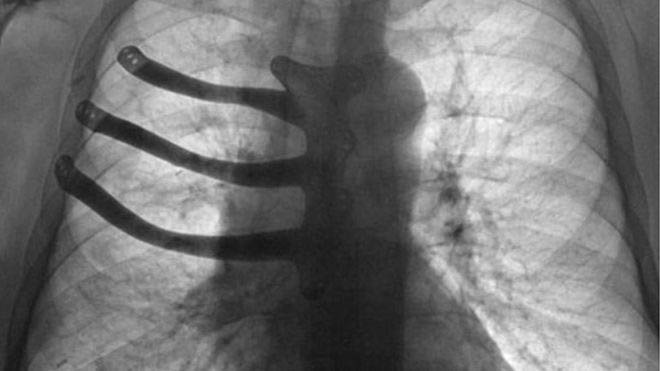

71-летнему Питеру Мэггзу удалили три ребра и половину грудинной кости, поместив вместо них протез.

Раковая опухоль разрослась величиной с теннисный мяч и ее удаление повлекло за собой обширные повреждения грудной клетки.

Но благодаря технологии 3D-печати врачи смогли изготовить для больного индивидуальный имплантат из титанового сплава.

Титановый имплантат изготовили заранее - по модели, которую подготовил доктор Голдсмит.